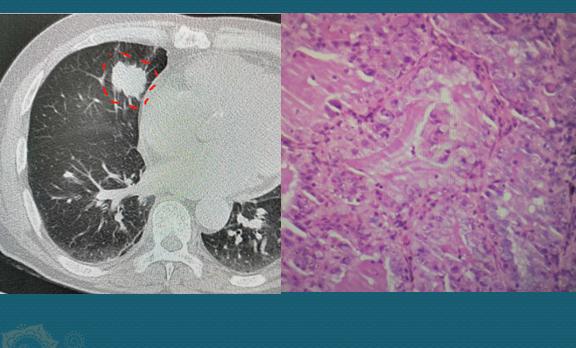

别埋怨豪大夫今天罗嗦,实在是有感而发!最近值班遇到一个年轻男子,才31岁,因为咳嗽发烧并逐渐胸闷,担心是病毒性肺炎过来检查,结果是肺腺癌,已经转移了:

31岁,肺癌转移

才31岁,右肺3.8cm的肺癌,已经侵犯胸膜引起胸腔积液和心包积液,还有纵隔多发淋巴结转移和淋巴管癌,没有根治机会了。快过年了……